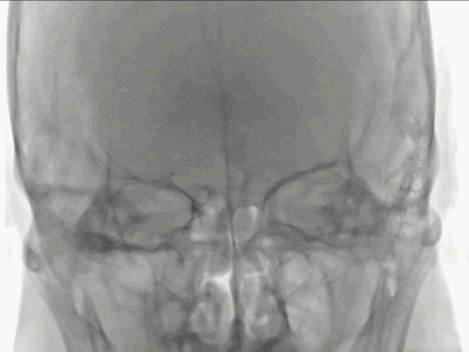

Catalyst 7抽出大量负荷血栓,大脑中动脉上干仍未显影。

微导丝微导管超选至大脑中动脉上干,微导管造影确认在血管内真腔内,释放Solitaire 4×20mm。

Solitaire 4×20mm支架锚定Catalyst 7抽吸导管到达M1段,抽吸导管负压,拉出取栓支架,取栓过程中Catalyst 7维持稳定。

两次支架取栓取栓取出血栓,血管再通。